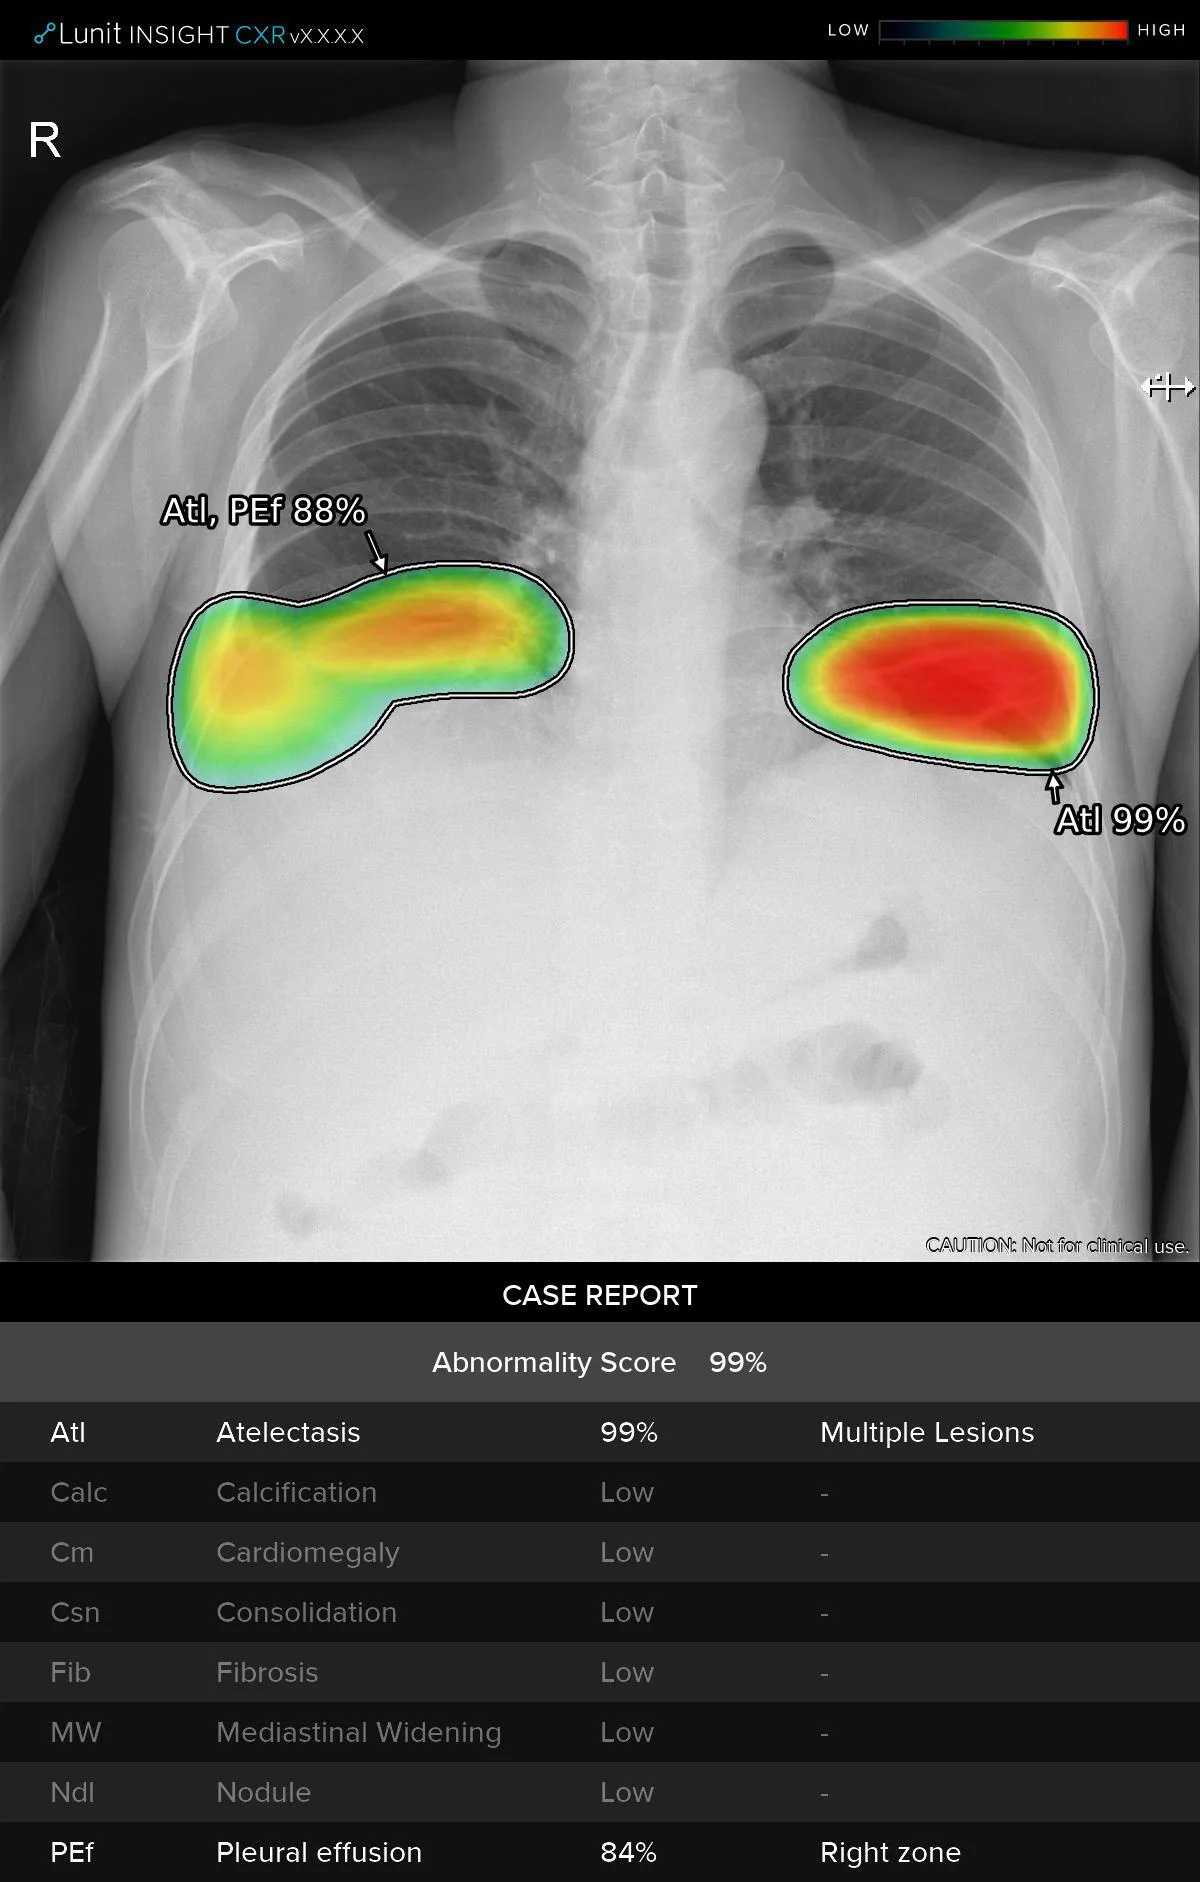

·ç´Ö, GEÇコÄÉ¾î º»»ç¿Í ÆÄÆ®³Ê½Ê ü°á

[µ¥Àϸ®¸Þµð ÇÑÇØÁø ±âÀÚ] ÀÇ·á AI ±â¾÷ ·ç´ÖÀÌ 19ÀÏ ¹Ì±¹ GEÇコÄÉ¾î º»»ç¿Í ÆÄÆ®³Ê½ÊÀ» ü°áÇß´Ù. ƯÈ÷ ÀÌ ÀÚ¸®¿¡¼­ µÎ ȸ»ç2020-06-19 19:12:50